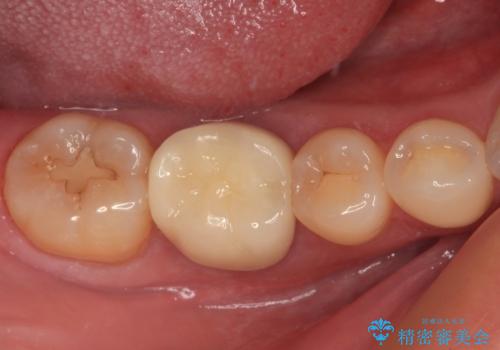

精密に治療を行うため、型取りを行った上でセラミックインレーによる修復治療を行うこととしました。

治療後は物が挟まることもなく、フロスが引っかかったり出血したりすることが減りました。